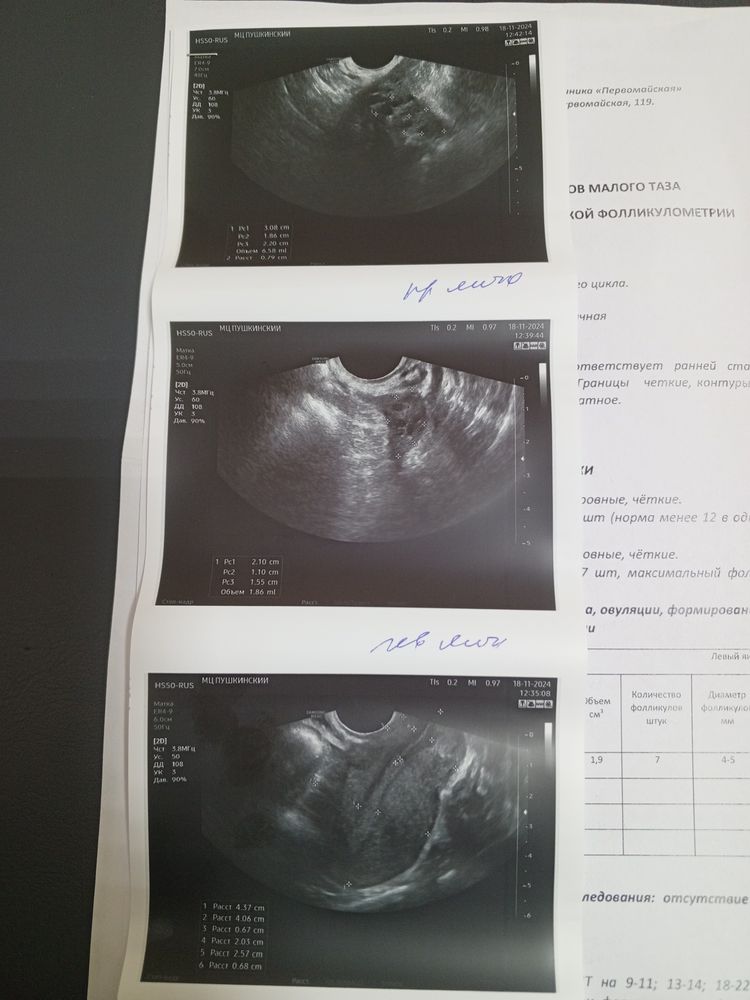

Яна, если честно, то УЗИ как будто не мое, фолликул больше чем до этого, хотя УЗИ девала часто, вот УЗИ с этого цикла